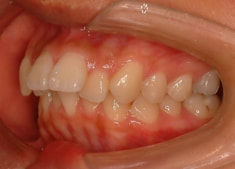

治療後(2年3ヶ月後)